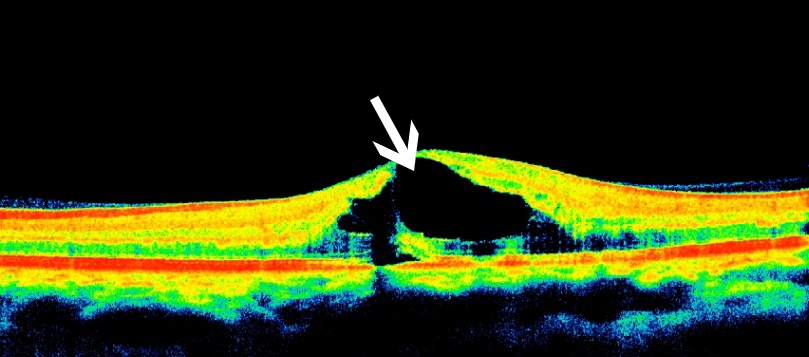

年龄相关性黄斑变性(湿性)

眼科ab超检查单怎么看常见眼底疾病检查结果的秒懂解读_https://www.jmylbn.com_新闻资讯_第23张眼科ab超检查单怎么看常见眼底疾病检查结果的秒懂解读_https://www.jmylbn.com_新闻资讯_第7张眼底彩照:黄斑区出血,出血周边呈黄白色

眼科ab超检查单怎么看常见眼底疾病检查结果的秒懂解读_https://www.jmylbn.com_新闻资讯_第25张

OCT:黄斑区神经上皮层轻度隆起,下方有黄色高反射的出血及新生血管,呈纺锤状

图片来源:天津市眼科医院